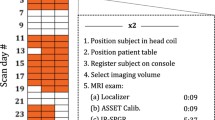

During both MRI scan sessions, the participants underwent a whole-brain 3D T1-weighted (Grabner et al. 2006) and a brainstem-zoomed T1-weighted turbo spin echo (TSE) structural scan (Sasaki et al. 2006) in a 3 T-TX Philips scanner equipped with a 32-channel head coil. The whole-brain volume (field of view (FOV): 224 × 177.33 × 168 mm; 140 slices; 0.87 × 0.87 × 1.2 mm; TR: 9.7 ms; TE: 4.5 ms; flip angle 8o; acquisition matrix: 192 × 152; scan duration: 4.9 min) was used to facilitate co-registration between scan sessions and subsequent normalization to the standard 0.5-mm MNI template. The TSE scan sequence was used to detect the LC and had similar sequence parameters as the ones reported in prior literature (FOV: 180 × 180 × 22.95 mm; 14 slices; reconstruction resolution 0.35 × 0.35 × 1.5 mm, gap of 10%; TSE factor: 3; TR: 500 ms; TE: 10 ms; flip angle 90o; acquisition matrix: 256 × 204; scan duration: 7 min) (see Fig. 1 for an example).